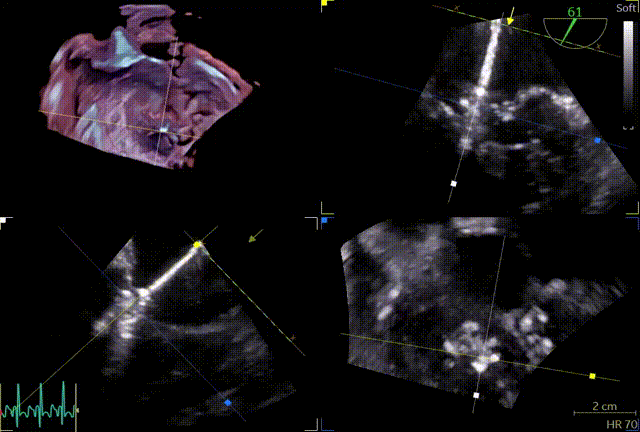

第一个夹子XTW

关小夹子,进入到左室后,跨瓣越过瓣叶尖端后,立马打开夹子,三维再次确认夹臂方向未改变,慢慢往上提拉,一次准确捕获瓣叶,前后叶Bouncing明显,后叶接近根部,关紧夹臂,反流量整体减少,但是内外侧都残余反流,内侧为主。反流明显减少,后叶夹持10mm以上,夹子稳定性良好,跨瓣压差小于3mmHg,决定释放。

释放前评估

释放后